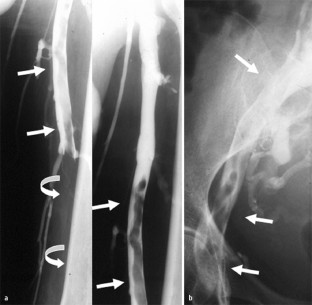

Abb. 1

Abb. 2

Abb. 3

Abb. 4

Abb. 5

Abb. 6

Abb. 7

Abb. 8

Abb. 9

Abb. 10

Abb. 11

Abb. 12

Abb. 13

Abb. 14

Abb. 15

Abb. 16